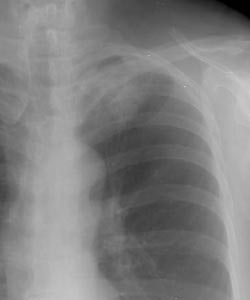

Example 1: In this case the patient had a large left upper lobe adenocarcinoma which was abutting the pleural surface on CT (Click here to view the patients CT scan). During percutaneous biopsy of the lesion, the patient developed a pneumothorax (white arrows) and the lesion could be seen to fall away from the lung apex indicating that there was no chest wall invasion. Although not intentional, a post-procedure pneumothorax can sometimes provide useful information.